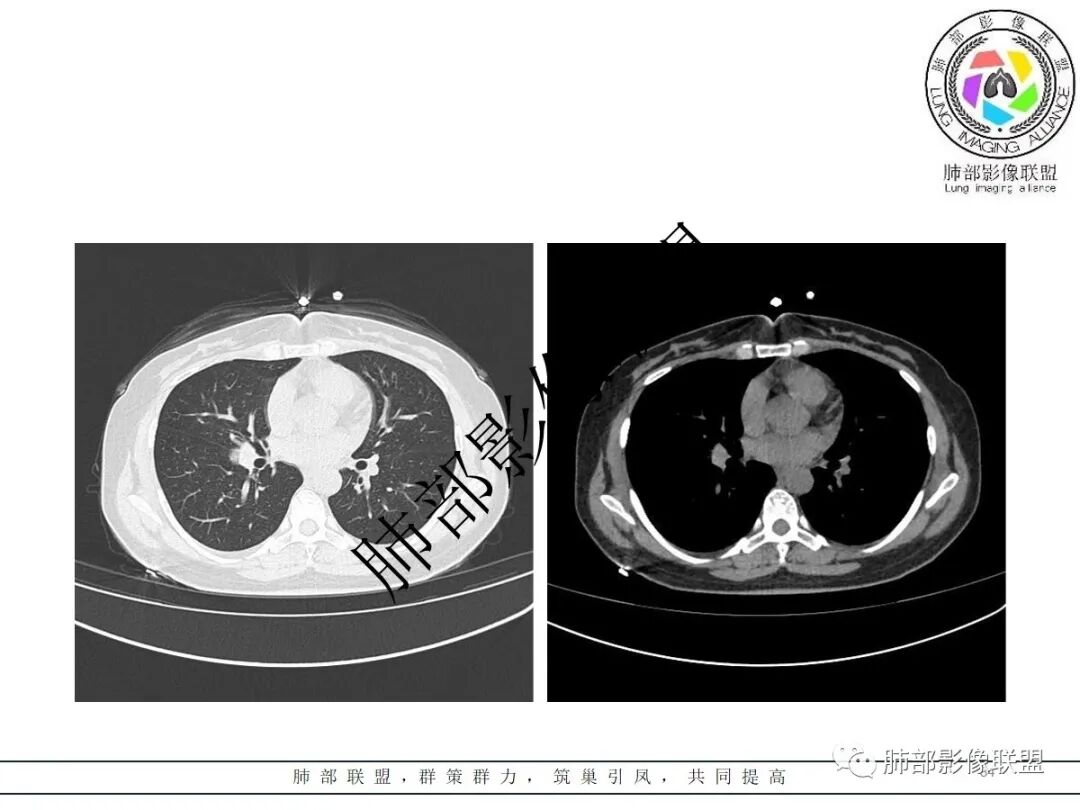

右肺门类圆形实性肿块,边缘光滑,无分叶毛刺,跨叶,推移血管,密度均匀,增强延迟强化相对明显,未见坏死及血管造影征。

2.右肺水平叶裂斜叶裂肺门交界区类椭圆形块影,表面光整,未见分叶毛刺及棘状突起,未见邻近结构牵拉。与邻近支气管无关联。

3.病灶密度均匀,未见液化坏死、钙化及脂肪低密度。轻度强化,可见纤细血管影蜿蜒穿行。右肺动脉推移变形,未见侵入或充盈缺损。

4.灶周未见磨玻璃晕或极低密度影环绕。右肺下叶背段胸膜下见微小实性密度结节影,边界清楚。

5.双肺门及纵隔未见增大淋巴结。双侧胸腔未见积液。